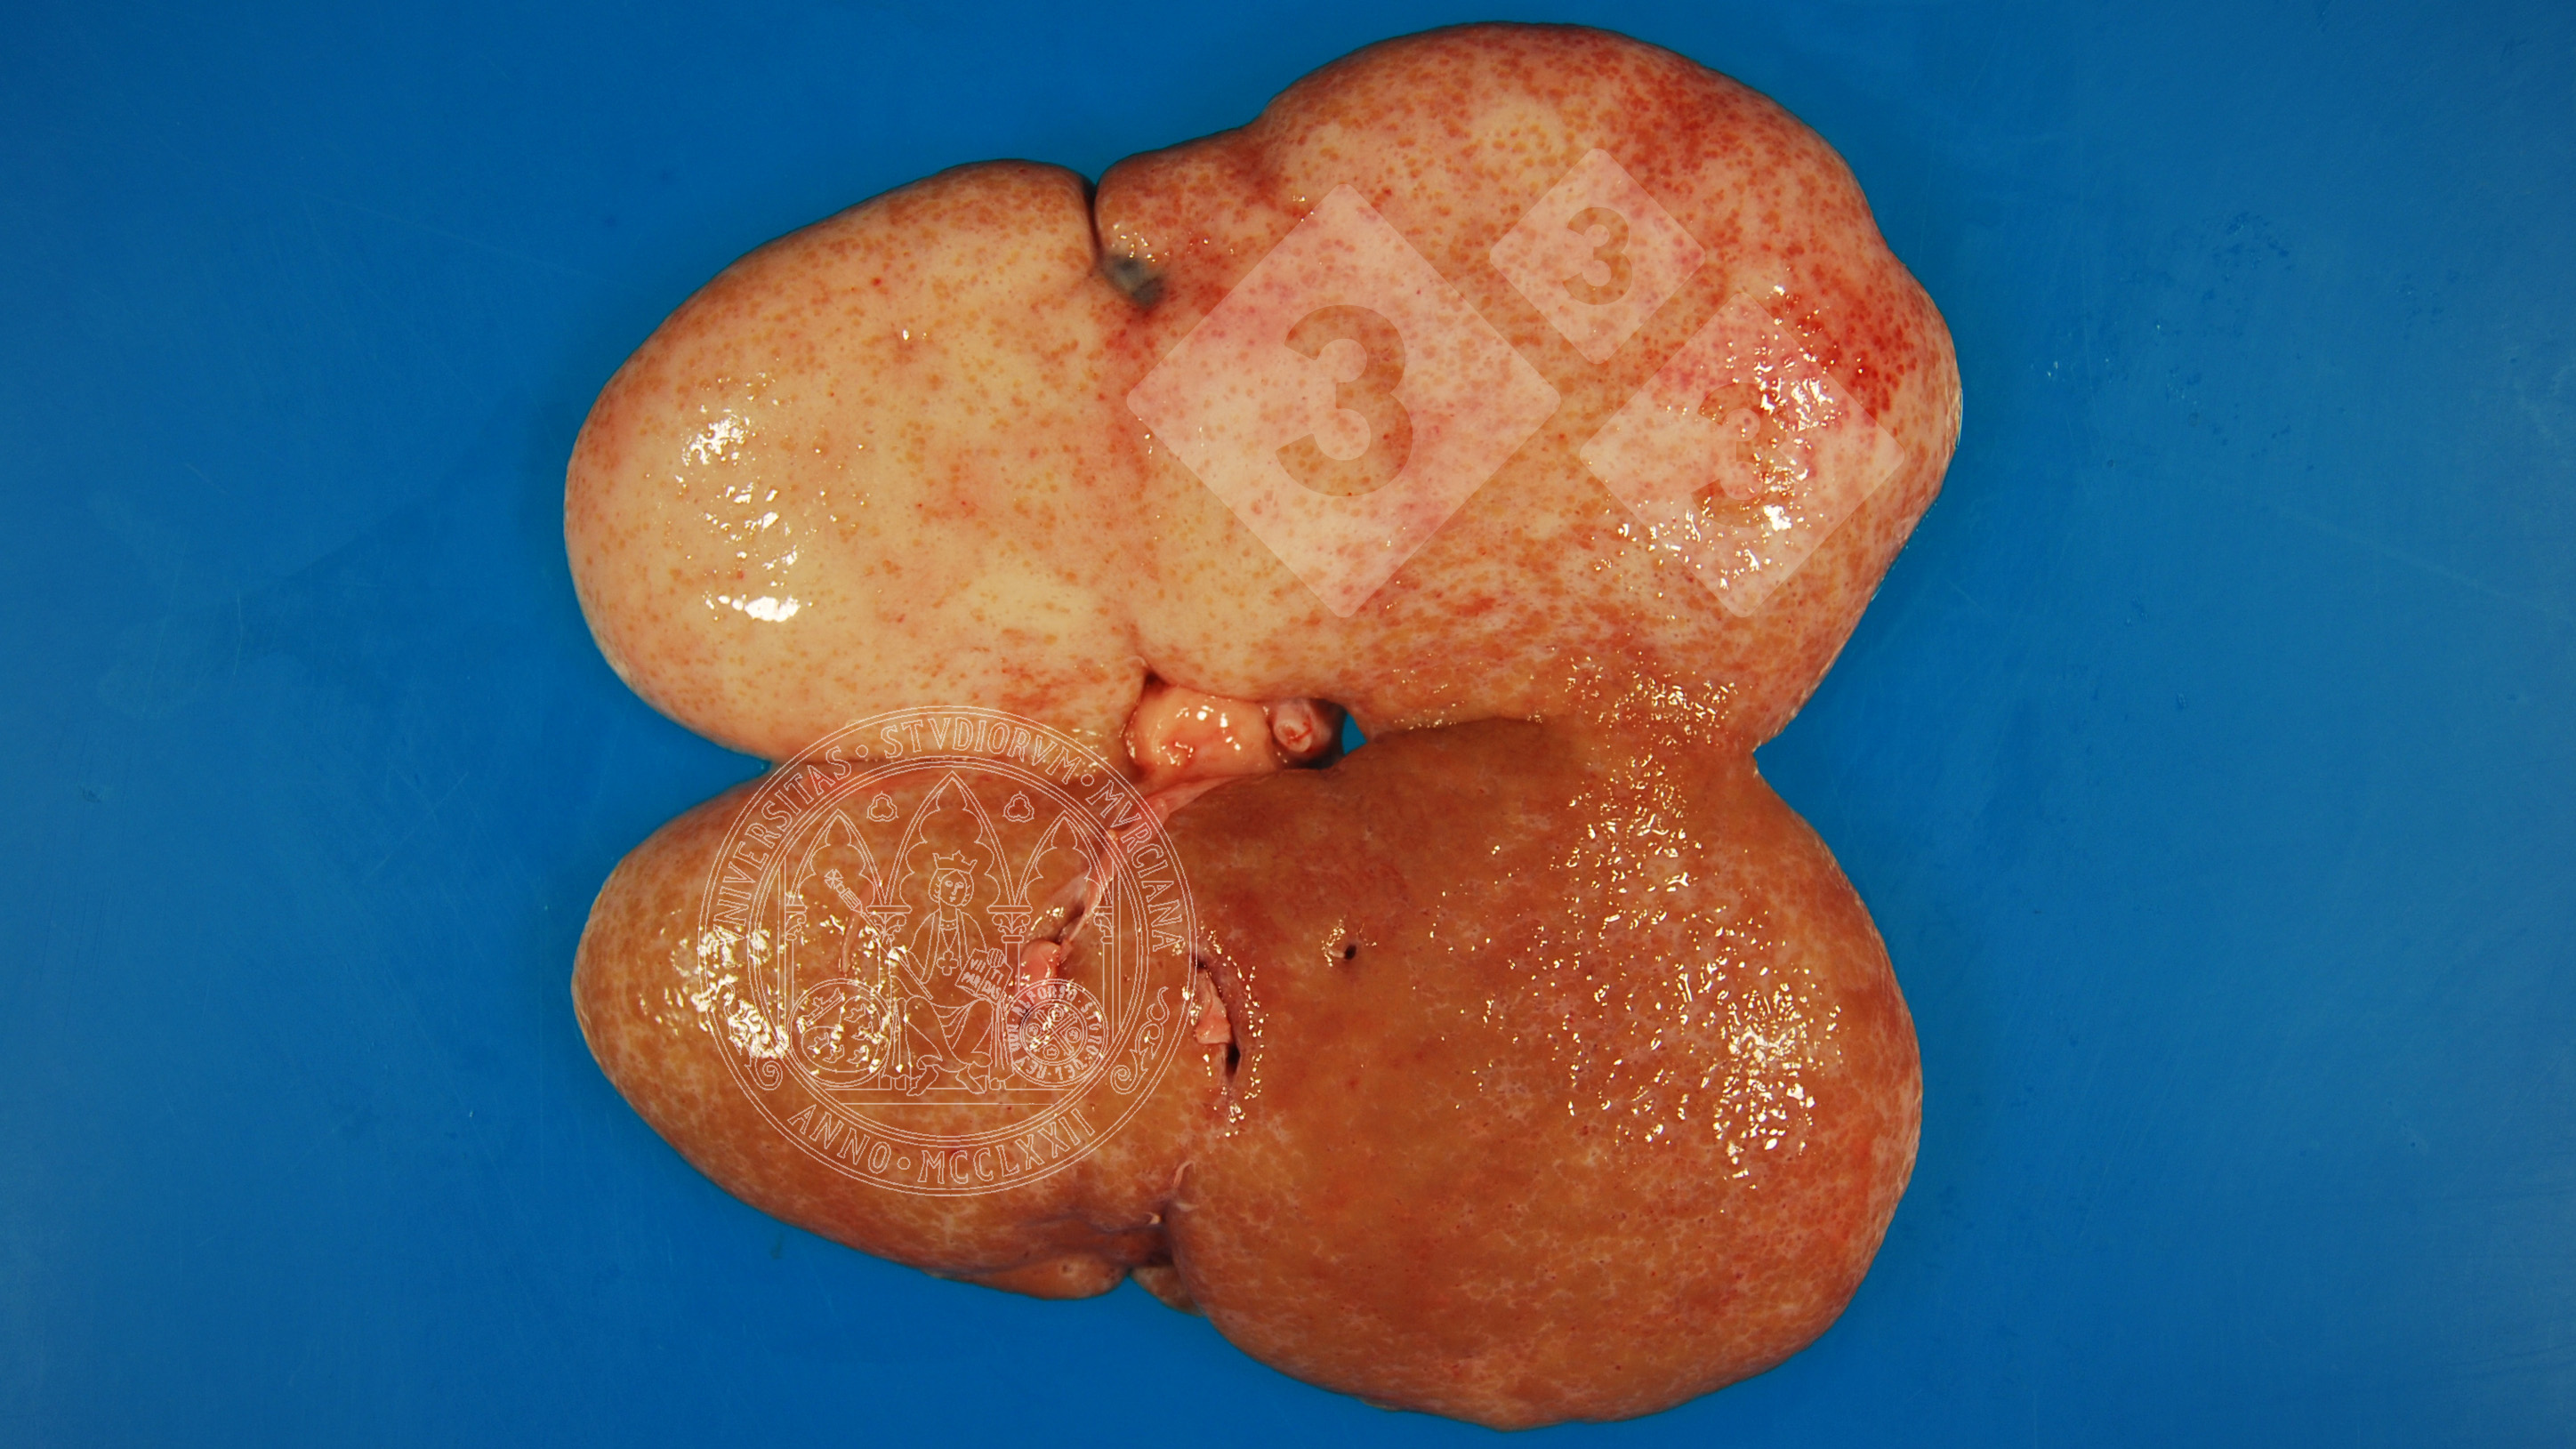

Riñón abierto de un cerdo de cebo que aparece con una coloración blanquecina en gran parte de la superficie y unos contornos irregulares. Se trata de un proceso crónico de fibrosis (esclerosis) como evolución de una nefritis intersticial y clínicamente se asocia a insuficiencia renal crónica.

Debemos diferenciar esta lesión de otros procesos inflamatorios crónicos o degenerativos.